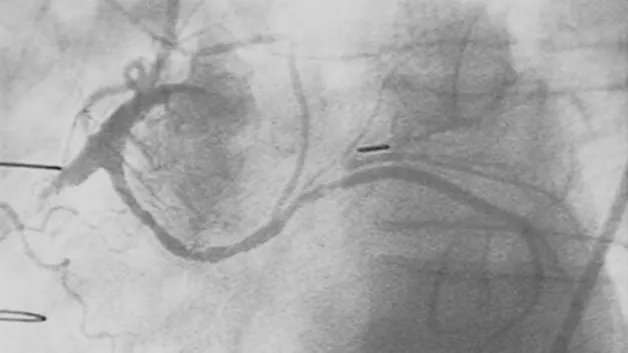

Тромбы, называемые «тихими убийцами», могут внезапно нарушить привычный образ жизни человека. Одним из провокаторов опасного состояния считается курение, предупредила кардиолог и академик РАН Елена Голухова в беседе с сайтом KP.RU.

Как пояснила специалист, тромбы, угрожающие здоровью и жизни, возникают при сочетании трех факторов, известных как «триада Вирхова». Речь идет о повреждении сосудов, замедлении кровотока и сбоях в системе свертываемости крови.